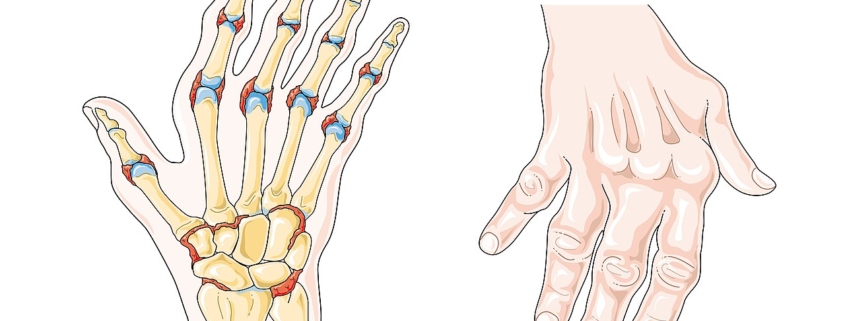

Rheumatoid arthritis (RA) is a chronic, inflammatory disorder affecting more than 1.3 million people in the United States alone. It primarily affects the joints, causing swelling, stiffness and pain. Over time, this condition can lead to joint damage or deformity. Understanding this condition can help patients manage its symptoms effectively.

Rheumatoid arthritis symptoms may vary in severity and may include:

- Joint pain and swelling

- Joint stiffness, particularly in the morning

Less common symptoms may include dry eyes and mouth, nodules under the skin, and inflammation in the lungs or heart.

Rheumatoid arthritis is typically diagnosed through a combination of physical examination, blood tests, and imaging, such as X-rays and ultrasound. The doctor will look for signs of inflammation as well as assess your joint function.